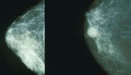

Результаты нового исследования могут помочь в лечении и предотвращении развития метастатического рака молочной железы.